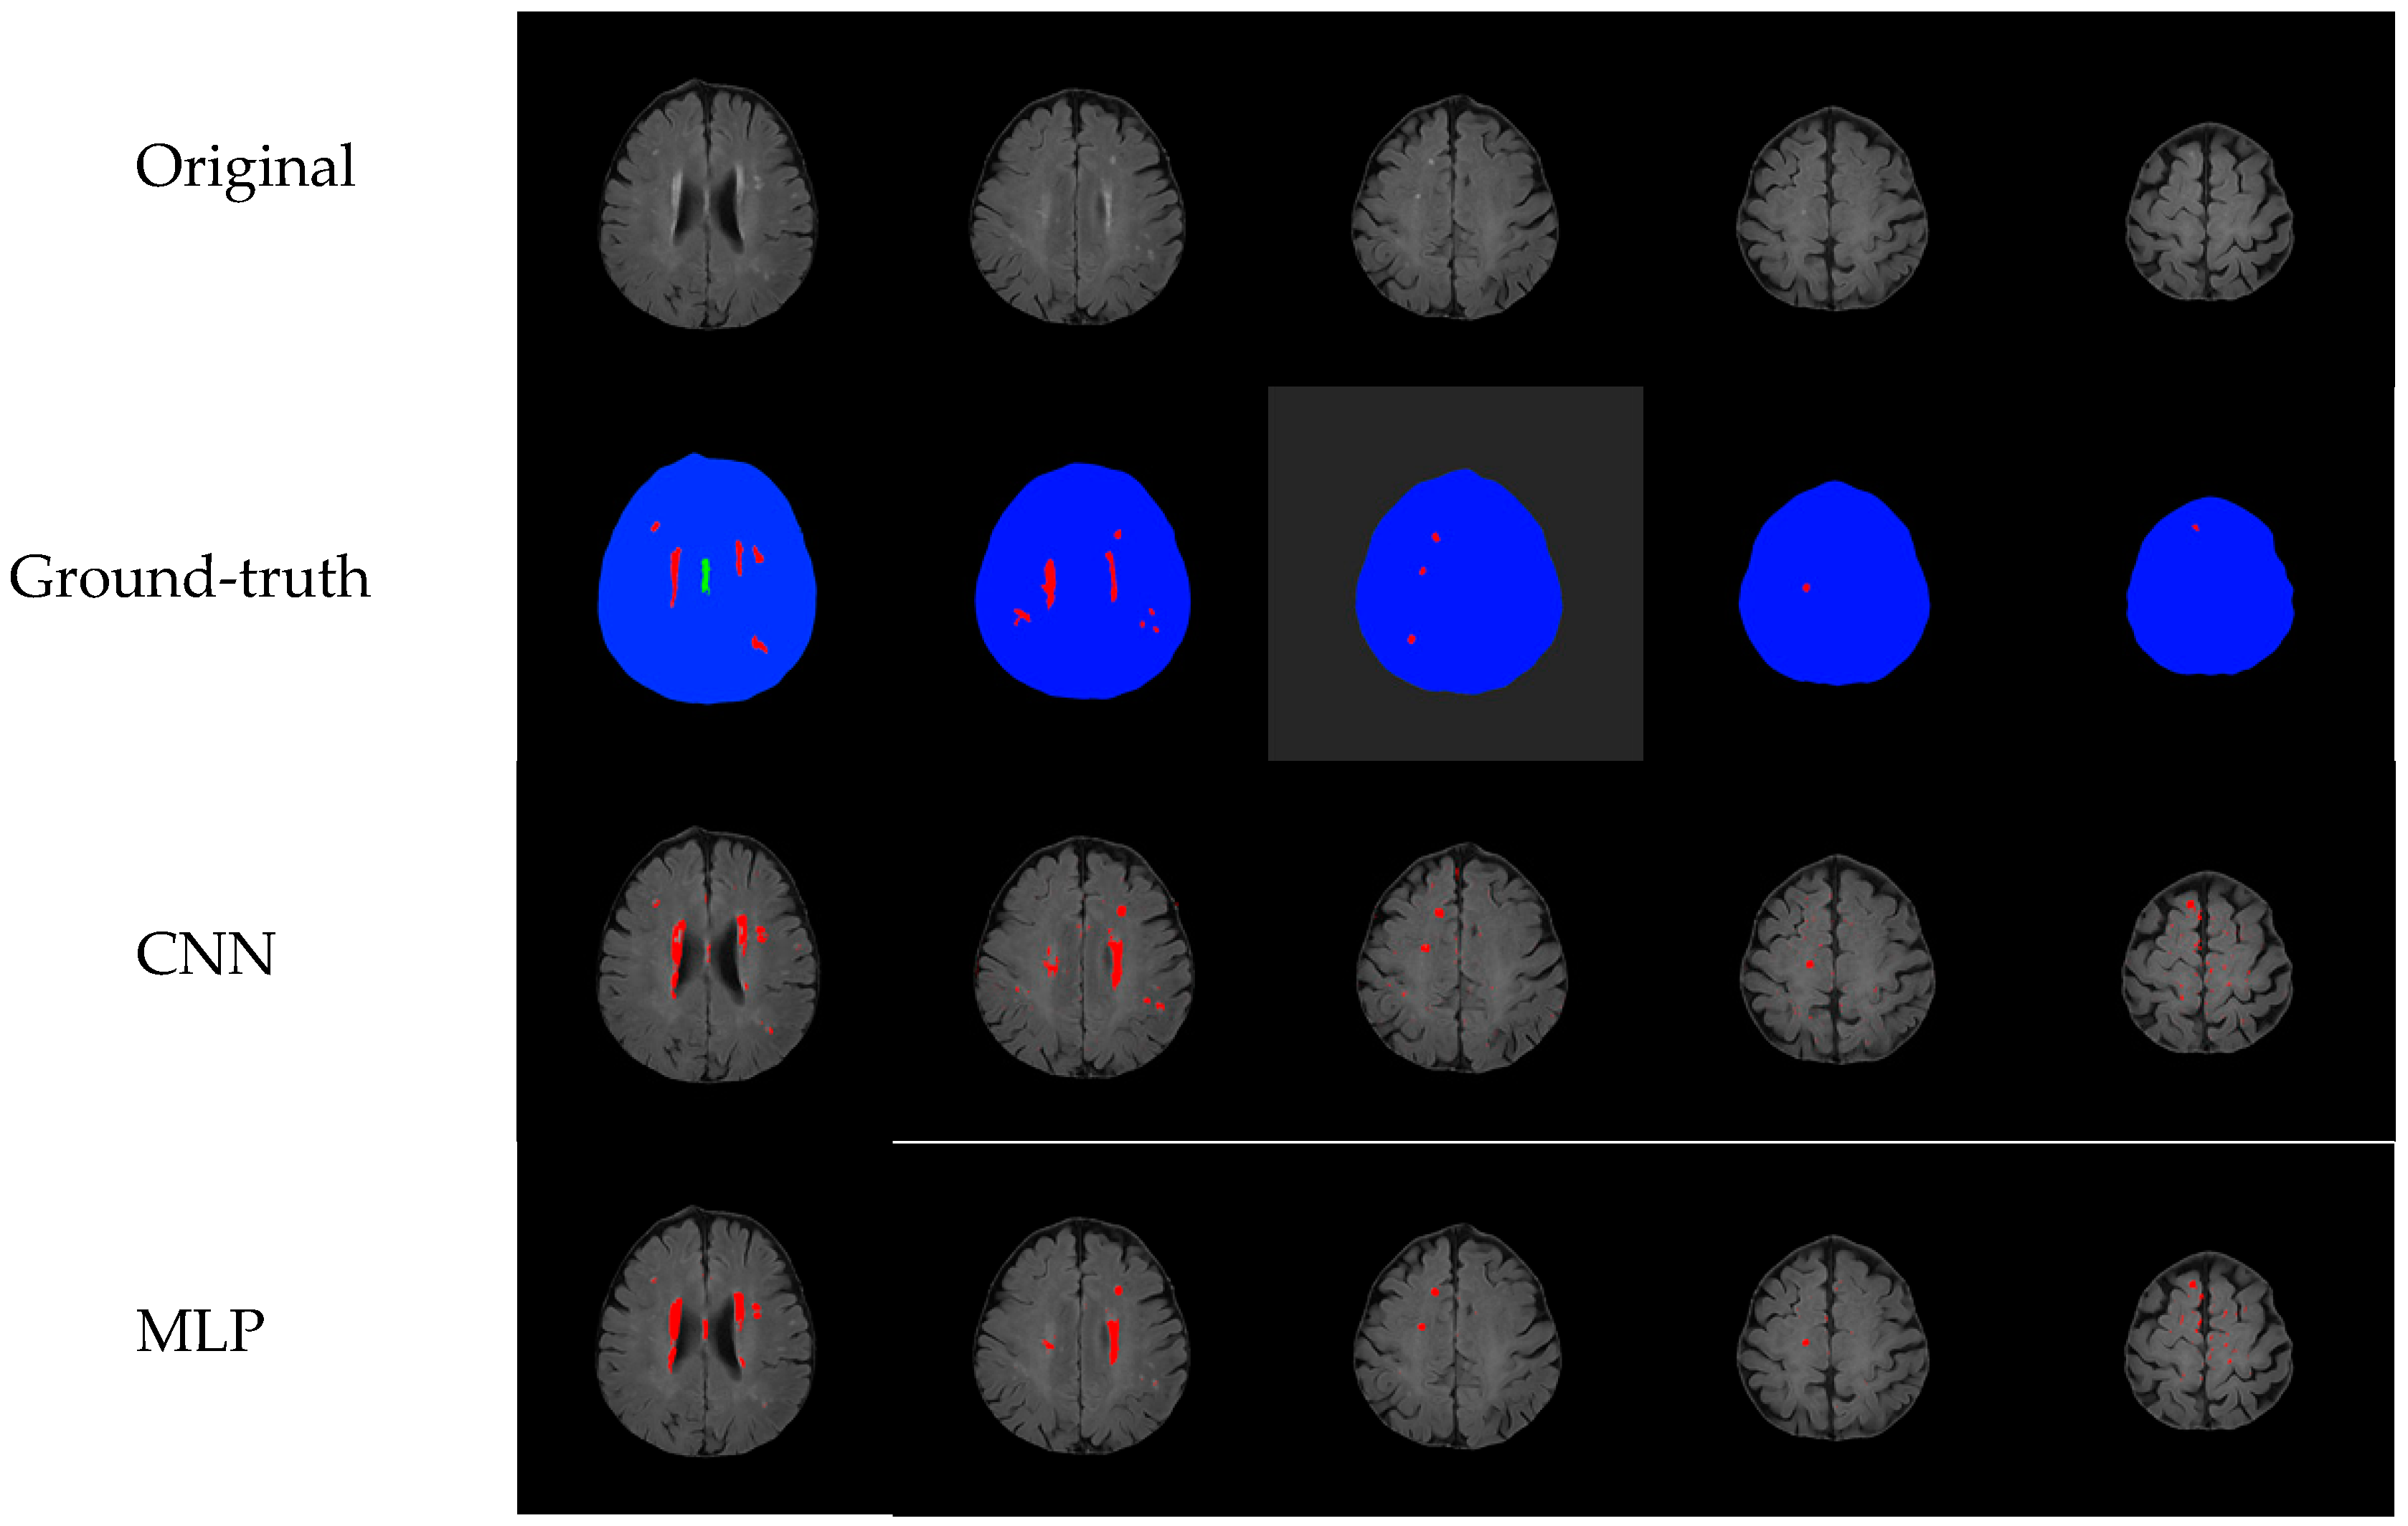

Comparison with Other Training Models